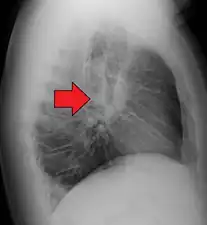

Hilar adenopathy especially on the person's left (AP CXR)

Hilar adenopathy especially on the person's left (lateral CXR)

Hilar adenopathy especially on the person's left (coronal CT)